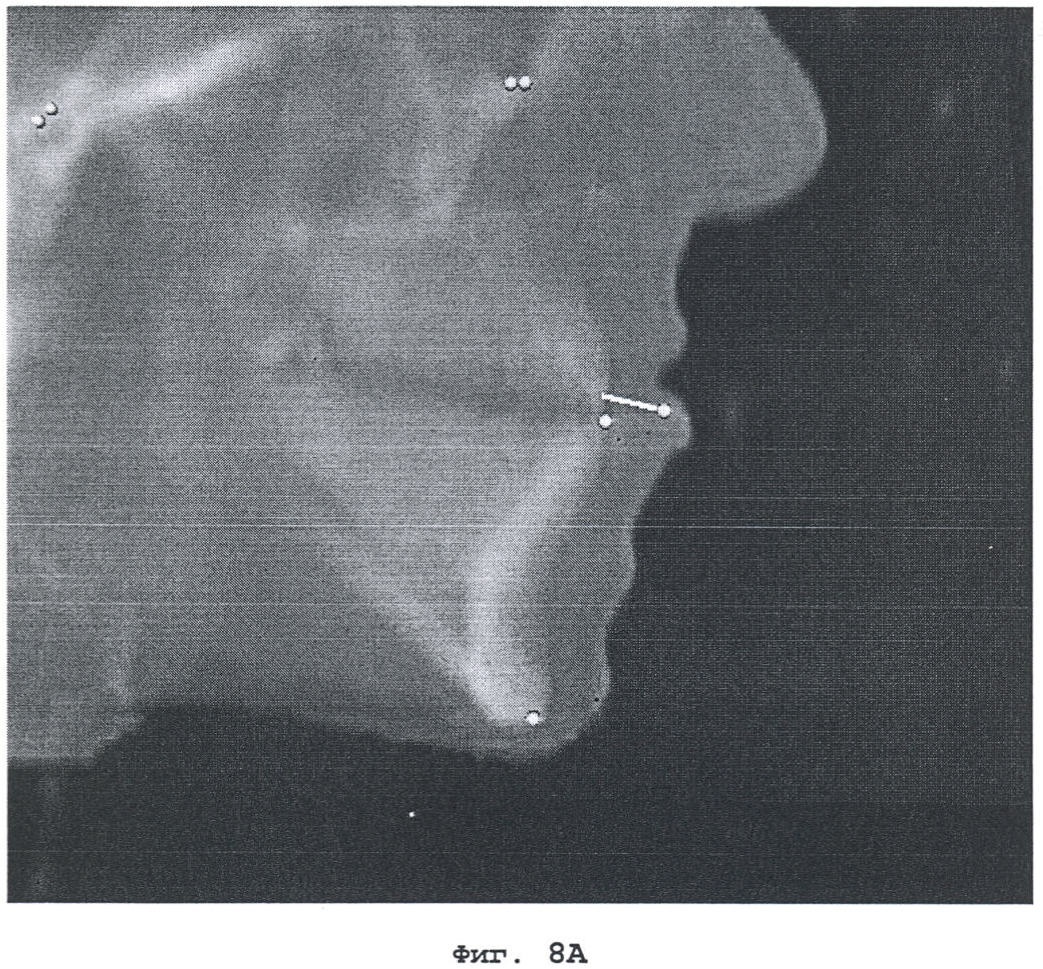

На фиг.3А и 3В показано задание анатомических ориентиров. Для точного определения точек используются как цефалограмма в боковой проекции, так и трехмерная модель костной поверхности.

На фиг.8А, 8В показано отслеживание перемещений ориентиров на виртуальных цефалограммах (фиг.8А) и на изображениях костной поверхности (фиг.8В).

Для создания максимально удобных условий работы пользователь может задать в рамках компьютеризованной системы планирования ортогнатической хирургии различные типы оперативного вмешательства – перемещение верхней челюсти, перемещение нижней челюсти, расширение нижней челюсти и т.д. При выборе типа хирургической операции на экране дисплея появляется пользовательский интерфейс, запрашивающий выполнение нескольких задач. В конце этого процесса хирург может ввести особые хирургические параметры, в результате чего происходят соответствующие перемещения костных фрагментов (фиг.7). На фиг.7 приведены параметры, относящиеся к перемещению верхней челюсти относительно анатомически заданной системы координат. При этом выполняется соответствующая корректировка ориентиров и описывается их перемещение относительно исходного положения (фиг.8). Для того чтобы можно было повысить гибкость средств репозиции костей в рамках системы планирования, пользователь может задать свой собственный набор исходных точек отсчета для перемещения костей, что позволит ему следовать выбранной методике работы и эффективно провести оперативное вмешательство.